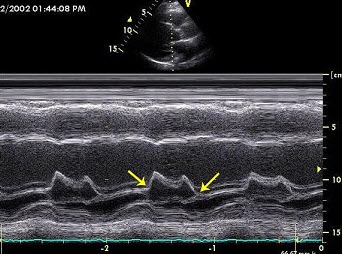

21、单项选择题 M型超声显示二尖瓣前叶DE幅度减低,EF斜率减慢,EPSS增大且前后叶呈同向运动,此时最可能的诊断是()

D.1.5~2.0